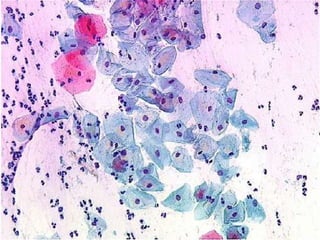

DYSPLASIA / CIN / SIL

INFILTRATION